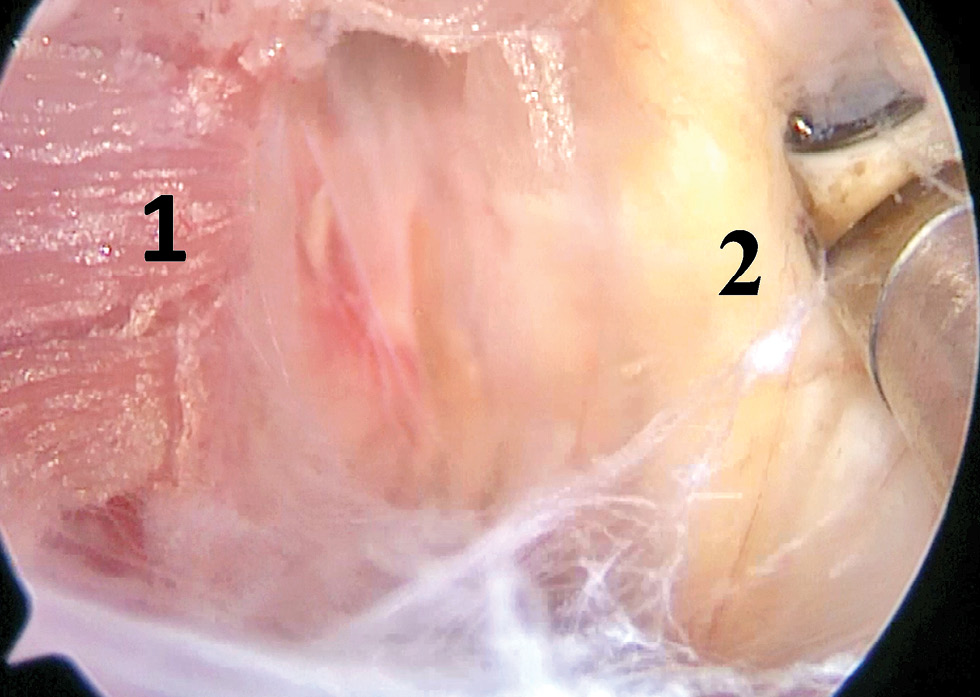

Кзади от ПС визуализировали среднюю лестничную мышцу (рис. 11).

Рис. 11. Средняя лестничная мышца (1) и средний ствол плечевого сплетения (2).

Fig. 11. Median scalene muscle (1) and median trunk of brachial plexus (2).

Декомпрессия сплетения заключалась в рассечении всех спаечных и рубцовых тканей кпереди, кверху и кзади от стволов ПС. Это позволило сформировать свободное пространство вокруг ПС для устранения его компрессии и ирритации. Интраоперационные фото ПС после выполнения декомпрессии представлены на рис. 12, 13.

Рис. 13. Компоненты плечевого сплетения (*) в области межлестничного пространства после выполнения декомпрессии.

Fig. 13. Components of brachial plexus (*) at interscalene space after performing decompression.